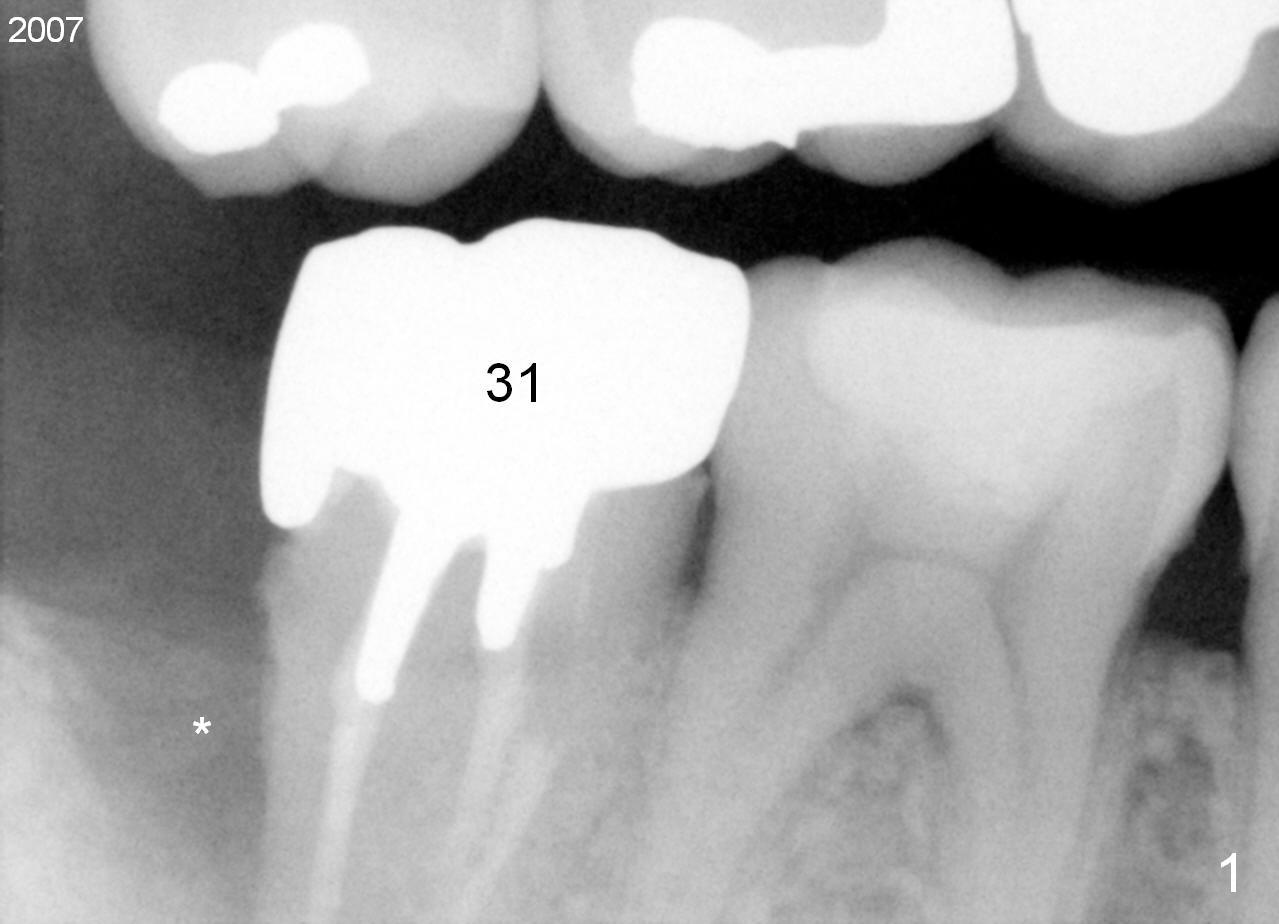

Complex Distal Defect

A 44-year-old man has had an asymptomatic distal defect of the tooth #31 for 8 years (Fig.1-5).  Recently there is an acute episode of swelling and pain.  A fistula develops mesiobucally.  Panoramic X-ray films tend to show that the distal defect is deep (Fig.2,5; yellow dashed line: upper border of the Inferior Alveolar Canal).  In addition, the distal defect may be not even buccolingually, as indicated by white and red arrowheads in Fig.3,4.  Following placement of a 6.9x10 mm bone-level implant, a 7.8x4 (4.5) mm cemented abutment is inserted for try in (Fig.6).  When it is fit, it is removed and a cover screw is temporarily placed.  A piece of Osteotape (~10x4 mm) is placed distobuccally or distolingually (depending upon which wall is lower).  A small amount of bone graft is packed between the most coronal portion of the implant and the Osteotape.  The cover screw is then removed and the abutment is re-inserted and tightened by hand.  An immediate provisional is fabricated with well-trimmed margin.  Reline is done if necessary for securely holding bone graft in place.  A new PA is to be taken prior to surgery to determine the extent of the lesion.  Photos are taken to show the mesiobuccal fistula.  Return to Lower Molar Immediate Implant Xin Wei, DDS, PhD, MS 1st edition 04/12/2015, last revision 05/25/2018